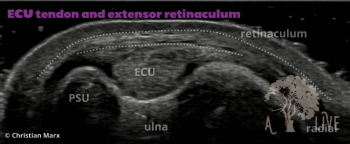

carpal ligaments